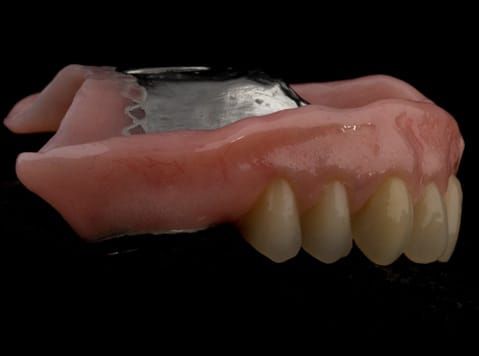

The 'gasket' or 'window' denture - provision of a maxillary cobalt chromium based partial denture

- Cobalt chromium reinforced gasket denture - using a Molloplast B "O" ring to retain and stabilise the denture. This was my professional preference as this was the least invasive and simplest solution to this dental problem. Should the UR7 require removal in the future - an artificial tooth could be added - resulting in a complete denture. The patient would have adapted to the denture fully by this stage and have good neuromuscular control of the prosthesis.

Following consultation and second discussion appointment the patient chose to have option 2 namely, a window denture - maxillary cobalt chromium based partial denture. The clinical situation and treatment process is shown in detail below with photographs. The patient was successfully rehabilitated with this and her quality of life considerably improved. The clinical work was provided by Finlay and the technical work by Rowan.